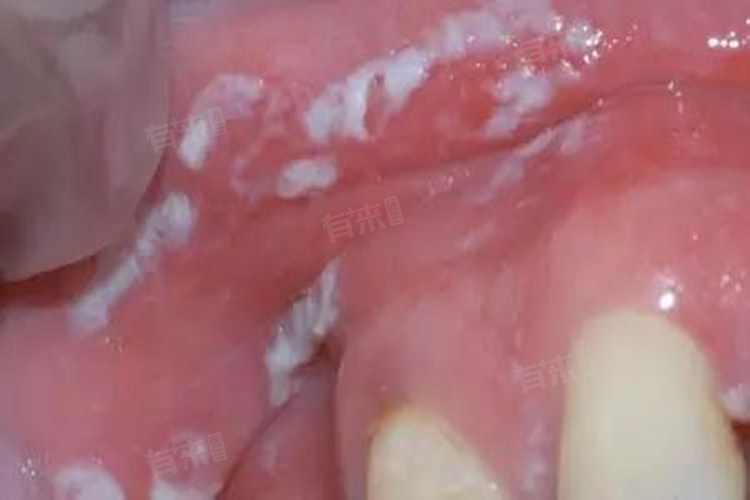

槟榔口腔白斑的自愈可能性因病情严重程度而异,对于轻度白斑,戒除槟榔并做好口腔护理后有可能自愈;而对于重度白斑,需要在医生的指导下进行综合治疗。

- 如果白斑症状严重,伴随局部组织的溃疡、疼痛或出血等症状,自愈的难度会大大增加。此时白斑可能已经发展为较为严重的口腔黏膜病变,患者需要在医生的指导下进行治疗,包括口服维生素A、维生素E等,外用维A酸乳膏或鱼肝油等药物,以及光动力治疗、激光治疗等。在严重情况下,可能还需要进行手术切除并做病理检查。